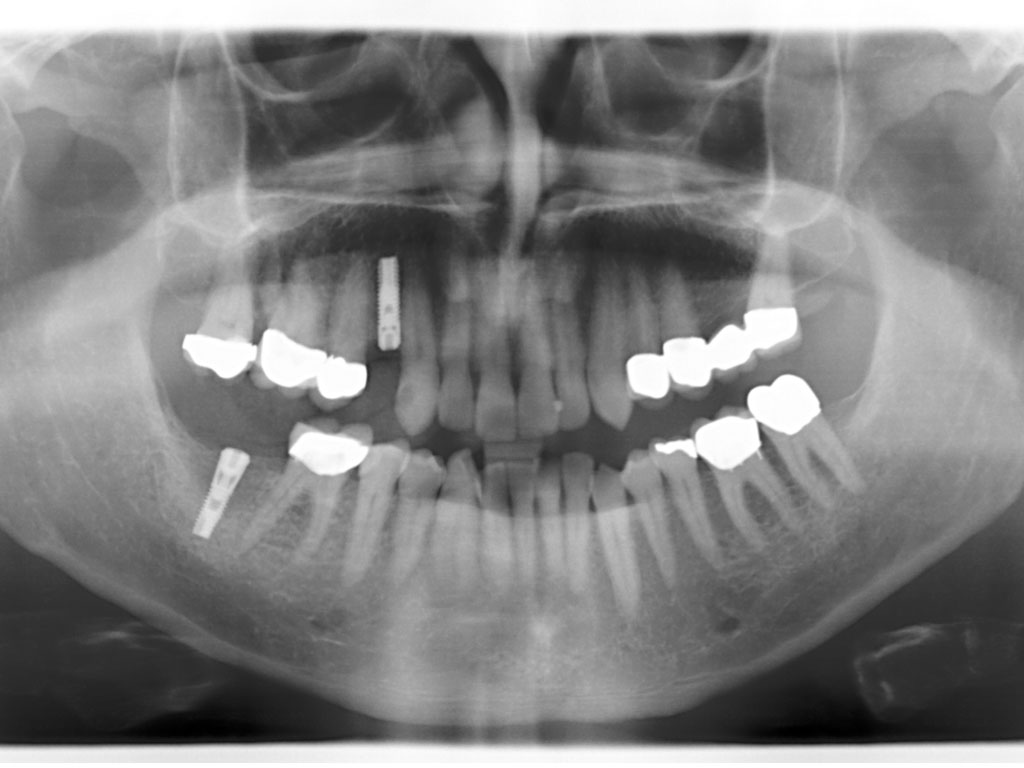

Digitales Röntgen

Das digitale Röntgen ist die modernste und strahlenärmste Methode der Röntgenaufnahme und hat gegenüber der klassischen Analogtechnik viele Vorteile: